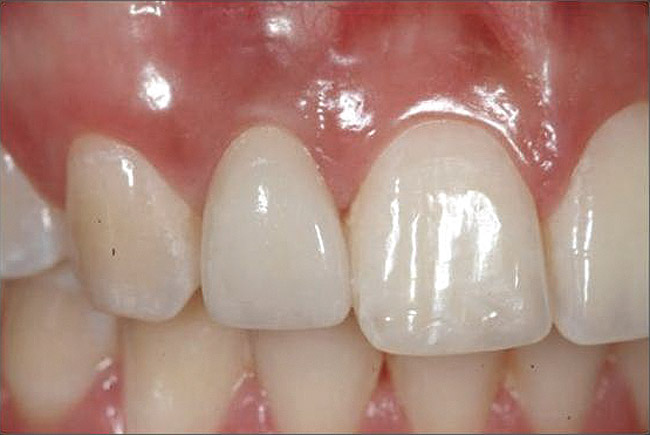

Figure 4  Characterization of the interproximal bone and tooth contacts: A periapical radiograph assists in measuring the distance from bone crest to the adjacent tooth contact points for missing tooth No. 8. The mesial bone crest to the adjacent tooth contact distance is < 5 mm, while the distal bone crest to adjacent tooth contact distance is > 6 mm (Fig 4). One-year following implant placement, conservation of these dimensions is revealed (Fig 5). The clinical photograph (Fig 6) of the lateral incisor adjacent to tooth No. 8 implant crown demonstrates that the absence of distal interproximal (papilla) fill related to the observed bone crest to contact distance exceeds 6 mm.

Figure 4

Figure 5  Characterization of the interproximal bone and tooth contacts: A periapical radiograph assists in measuring the distance from bone crest to the adjacent tooth contact points for missing tooth No. 8. The mesial bone crest to the adjacent tooth contact distance is < 5 mm, while the distal bone crest to adjacent tooth contact distance is > 6 mm (Fig 4). One-year following implant placement, conservation of these dimensions is revealed (Fig 5). The clinical photograph (Fig 6) of the lateral incisor adjacent to tooth No. 8 implant crown demonstrates that the absence of distal interproximal (papilla) fill related to the observed bone crest to contact distance exceeds 6 mm.

Figure 5

Figure 6  Characterization of the interproximal bone and tooth contacts: A periapical radiograph assists in measuring the distance from bone crest to the adjacent tooth contact points for missing tooth No. 8. The mesial bone crest to the adjacent tooth contact distance is < 5 mm, while the distal bone crest to adjacent tooth contact distance is > 6 mm (Fig 4). One-year following implant placement, conservation of these dimensions is revealed (Fig 5). The clinical photograph (Fig 6) of the lateral incisor adjacent to tooth No. 8 implant crown demonstrates that the absence of distal interproximal (papilla) fill related to the observed bone crest to contact distance exceeds 6 mm.

Figure 6